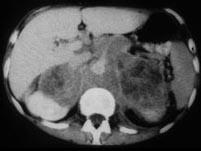

问题 男,76岁,全身浅表淋巴结肿大,请结合下列图片作出诊断 ( )

选项 A、肾上腺转移瘤 B、肾上腺淋巴瘤 C、肾上腺癌 D、肾上腺嗜铬细胞瘤 E、肾上腺腺瘤

答案 B